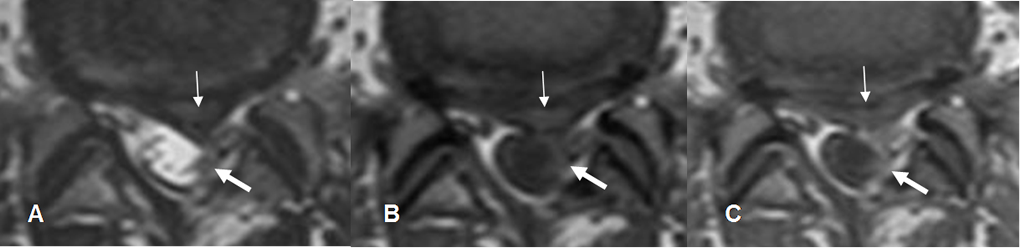

Fig 127. Compresión mixta.

A: RM axial en T2 y B: RM axial en T1. Laminectomía izquierda, con imagen de tejidos blandos de localización mediana y paramediana izquierda, que comprime el saco dural. (Flecha delgada).

C: RM axial en T1 con contraste. La lesión no realza con el contraste correspondiendo a recidiva de hernia, pero existe otra zona hipointensa que si realza y comprime el lado izquierdo del saco, por fibrosis. (Flecha gruesa).